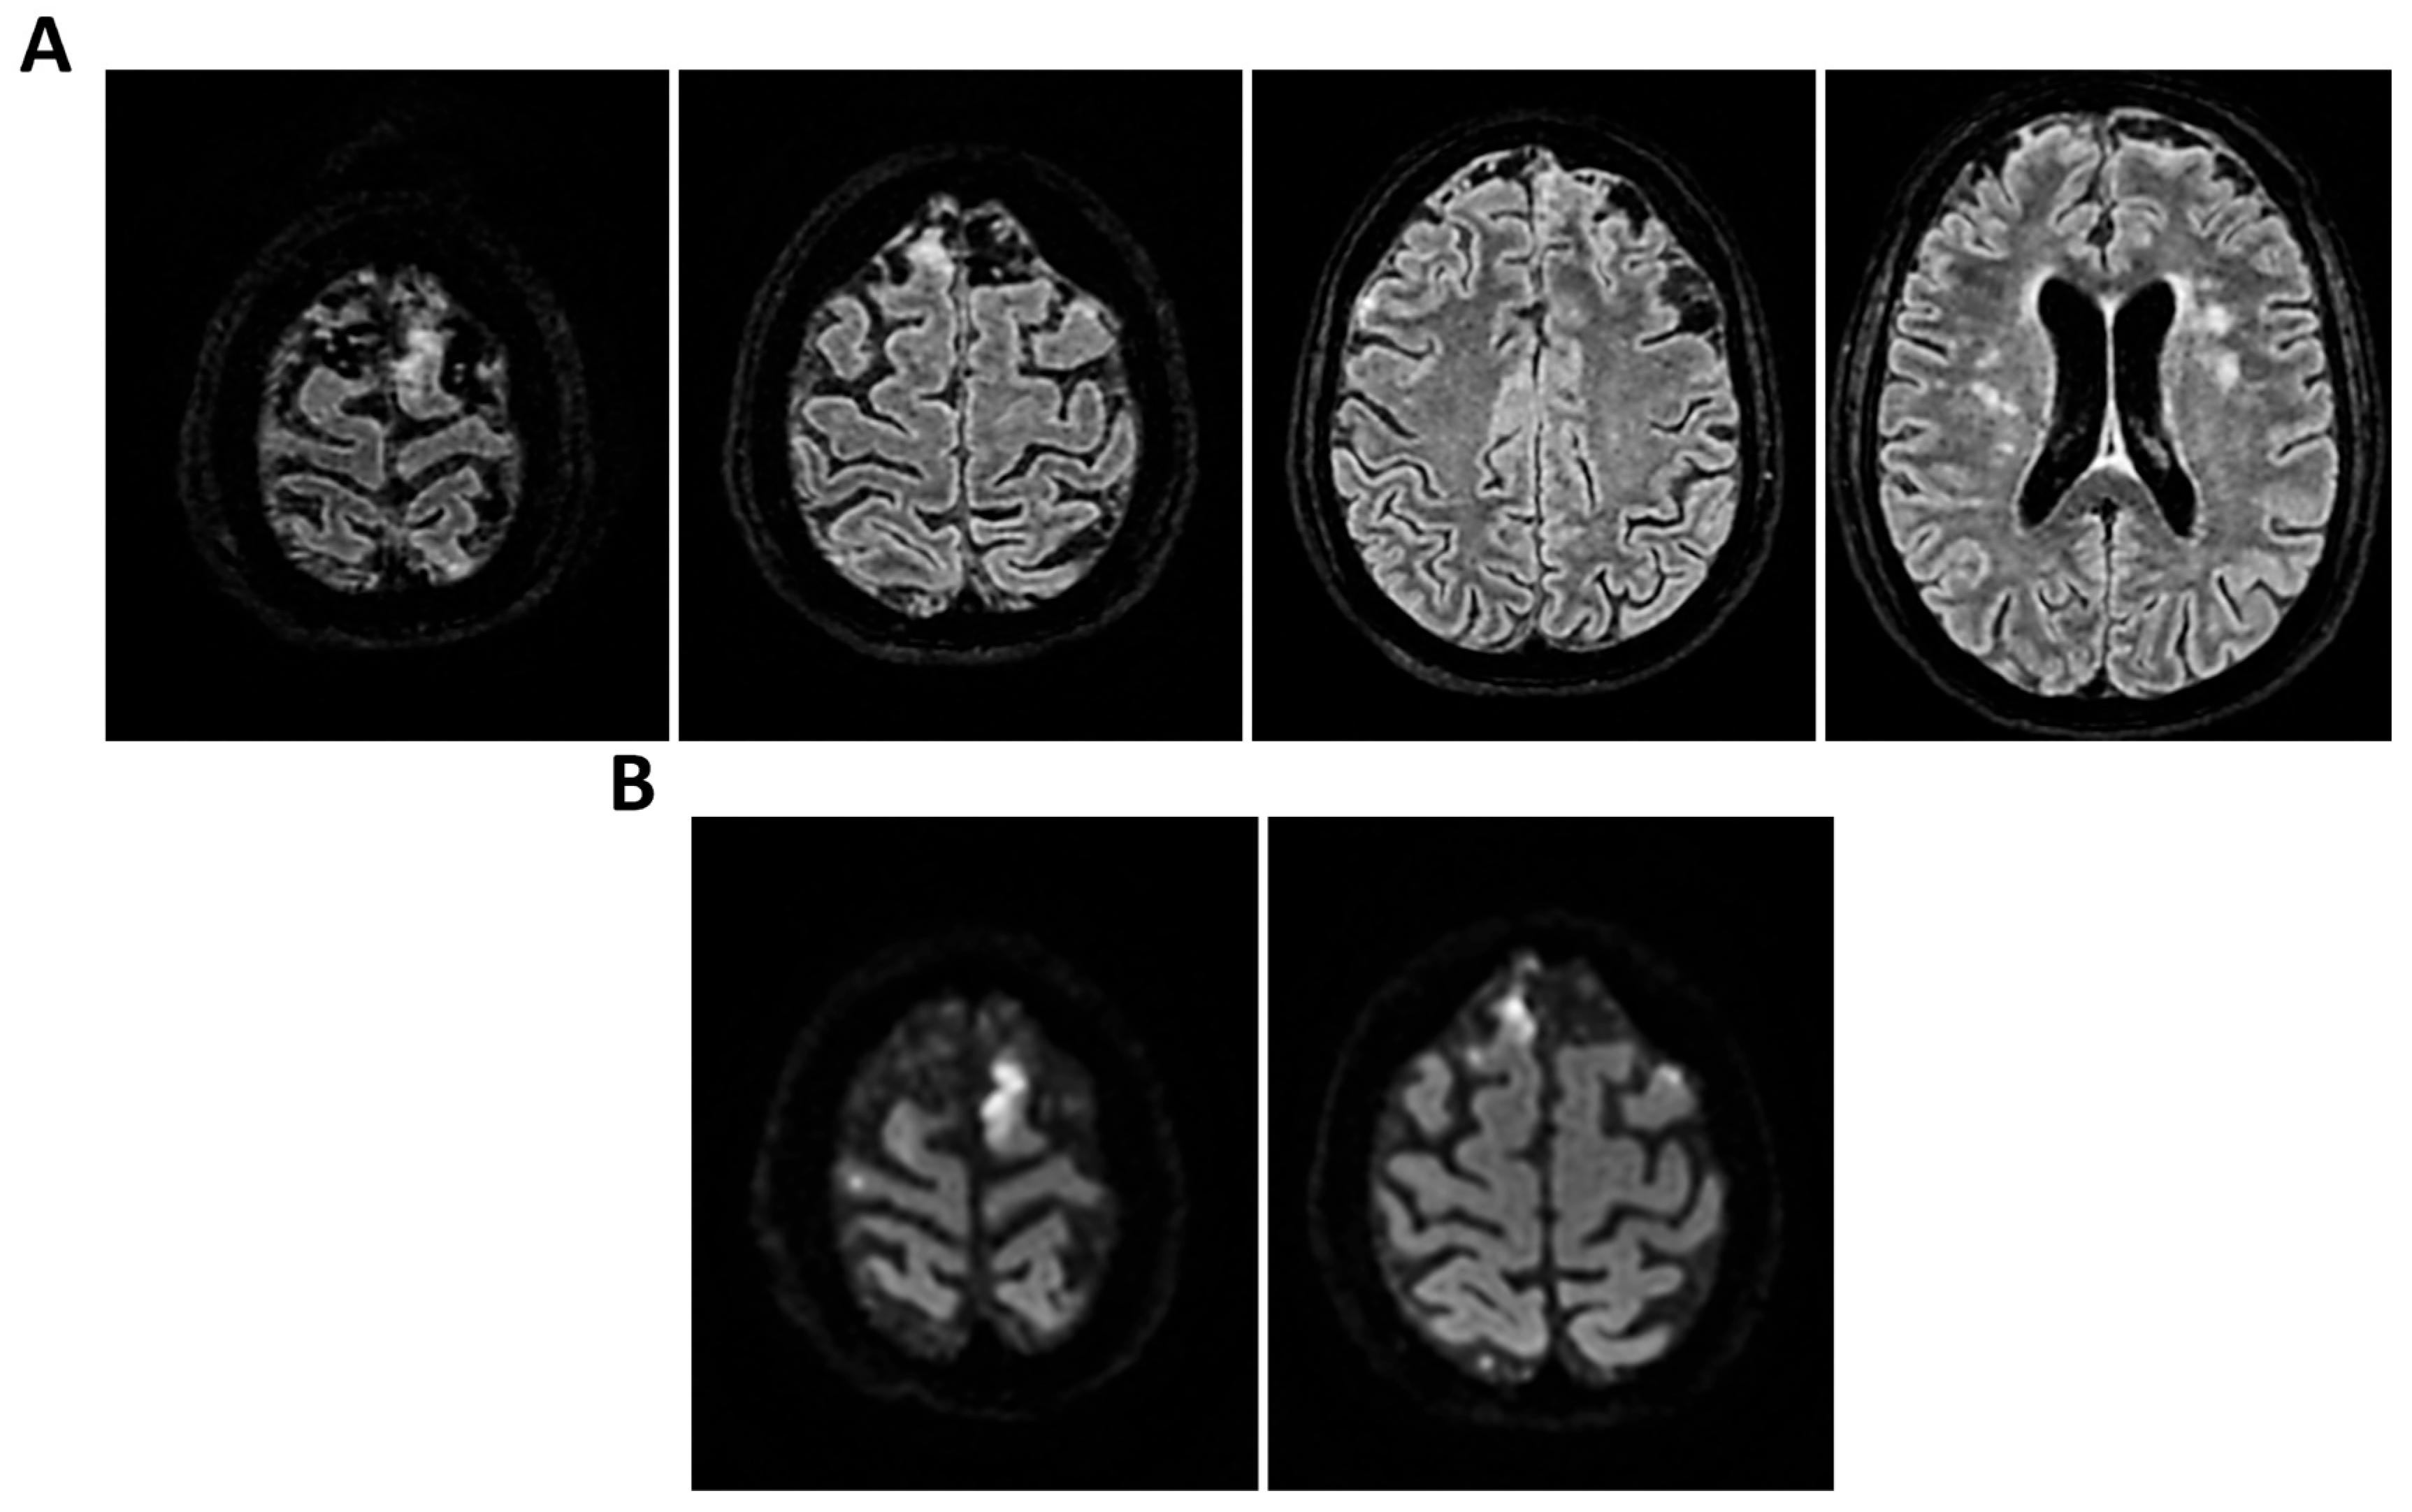

Figure 1.

MRI of patient 1 group 1. A 74-year-old woman with a history of atrial fibrillation, ischemic heart disease, anxiety-depressive syndrome, and hypertension was found at home in a stuporous state. She had experienced asthenia and fever in the preceding days and had initiated ciprofloxacin treatment. On arrival, laboratory exams showed leukocytosis (11,930/mm3, 90.4% neutrophils), elevated INR (1.92), and markedly increased inflammatory markers. Arterial blood gas revealed hypoxemia (pO2 55 mmHg), requiring mechanical ventilation with 35% FiO2. Brain CT was unremarkable, showing no acute lesions or signs of raised intracranial pressure. Chest CT revealed bilateral posterior-basal consolidations with air bronchograms (more severe on the left), a smaller consolidation in the left upper lobe, and bilateral pleural effusions, consistent with bronchopneumonia. A lumbar puncture was initially contraindicated due to coagulopathy. Due to worsening neurological status (GCS 6), the patient was transferred to the ICU, intubated, and underwent lumbar puncture. On day 2, TCCD showed PI values of 0.62 (right) and 0.71 (left), with no signs suggestive of intracranial hypertension. (A) 3D axial FLAIR sequence shows multiple bilateral hyperintense areas, without mass effect. (B) Some of these present diffusion restriction in axial DWI sequence with the largest located in the left middle and superior frontal gyrus. There is also a subtle pachymeningeal enhancement in the bilateral fronto-temporal region. Supratentorial and infratentorial ventricular system is normal in size and configuration, with no midline shift or hydrocephalus.

Figure 2.

MRI of patient 2 group 1. A 37-year-old woman presented to the emergency room (ER) with acute confusion and fever that began earlier the same day. Neurological evaluation and brain CT were unremarkable, as was chest CT. A lumbar puncture was performed. FilmArray was negative for bacteria but showed elevated cell count. Immunoglobulins for Clostridium tetani were administered empirically. The patient developed generalized myoclonic movements. EEG revealed epileptiform activity in the right frontotemporal region and diffuse cerebral slowing. Due to worsening neurological status, she was intubated and transferred to the ICU. On day 2 of ICU admission, transcranial Doppler TCCD showed pulsatility indices of 0.94 (left) and 0.89 (right), with no evidence of intracranial hypertension. (A) 3D axial FLAIR, (B) axial DWI and (C) 3D axial T1 FSPGR after administration of contrast medium show normal morphology and signal intensity of brain tissue. There is no evidence of acute or chronic infarction, demyelination or mass lesion. Supratentorial and infratentorial ventricular system is normal in size and configuration, with no midline shift or hydrocephalus. No signs of intracranial hypertension. Sulci and subarachnoid spaces are within normal limits for age.

Figure 3.

MRI of patient 3 group 1. A 49-year-old man with pneumococcal meningitis was transferred to INMI L. Spallanzani after 10 days of right-sided otalgia, fever, and headache. On arrival, he was alert and oriented but exhibited psychomotor slowing. Physical exam revealed positive Kernig’s, Brudzinski’s, and Lasegue’s signs. Brain CT was negative for acute lesions but showed bilateral maxillary sinusitis and right-sided otomastoiditis. Lumbar puncture revealed cloudy CSF with 4069 cells/mm3, low glucose (36 mg/dL), and elevated protein (180 mg/dL). FilmArray was positive for Streptococcus pneumoniae; urinary antigens for Legionella pneumophila and S. pneumoniae were negative. The patient was started on Vancomycin, Ceftriaxone, and Dexamethasone. The next day, he became mute and poorly cooperative, prompting transfer to the ICU. TCCD showed normal PI (1.18 right, 1.02 left) with no signs of intracranial hypertension. (A) 3D axial T1 FSPGR (Fast Spoiled Gradient Recalled) shows mild and diffuse increase in physiological pachymeningeal enhancement, with no specific significance. Morphology and signal intensity of brain tissue is normal. (B) 3D axial FLAIR confirms right-sided otomastoiditis and (C) bilateral maxillary sinusitis.

Figure 4.

MRI of patient 4 group 1. A 46-year-old HIV-positive woman with a history of substance abuse, alcohol use, heavy smoking, and on methadone therapy was admitted to the ER after a fall with head trauma. Cranial CT revealed a hypodense, heterogeneous lesion in the right nucleus-capsular region. Chest CT showed pseudonodular lesions, parenchymal consolidations (lingular and posterior-basal left lung), bilateral fibrous-scar tissue thickening, and polylobulated thickening in the right upper lobe. Due to respiratory deterioration, she was intubated and admitted to the ICU. Infectious disease consultation revealed severe immunosuppression (CD4 count 37/mm3), high HIV and HCV viral loads, and positive toxoplasmosis serology. She was not on antiretroviral therapy. Transferred to a specialized ICU, she was diagnosed with neurotoxoplasmosis. On day 2, TCCD showed altered CBF with PI of 1.96 on the right and 1.25 on the left, indicating possible intracranial hypertension. (A) 3D axial FLAIR sequence shows multiple bilateral supratentorial and infratentorial hyperintense areas. (B) Some of these areas present diffusion restriction in axial DWI sequence with the largest located in the right basal ganglia with moderate compression on the third ventricle. (C) One of these areas in the right middle frontal gyrus shows “ring enhancement” in the 3D axial T1 FSPGR after administration of contrast medium.

Figure 5.

MRI of patient 5 group 1. A 76-year-old diabetic woman was admitted to the ER for confusion, slurred speech, hyperglycemia, dyspnea (SpO2 87% on room air), and recurrent syncopal episodes, the latest resulting in a fall with frontal head trauma. Brain CT and neck vessel angio-CT were negative for acute lesions. Chest CT revealed a D11 vertebral collapse (post-vertebroplasty), right rib fractures (4th–7th), and right basal pleural effusion with ventilation impairment. During hospitalization, she developed fever and a right facial rash suggestive of herpes zoster. Empiric therapy with Tazocin and Zovirax was started, later broadened to include Rocephin and Ampital. On day 4, the patient experienced a decline in consciousness, necessitating intubation and mechanical ventilation. CSF analysis via lumbar puncture was positive for Varicella Zoster virus (FilmArray). She was transferred to a specialized ICU. On the second day in the ICU, TCCD showed severe CBF alteration, with a PI of 3.6 and markedly impaired flow in the left MCA, indicating likely intracranial hypertension and poor perfusion. (A) 3D axial FLAIR sequence shows subtle soft hyperintensity in the right hippocampal region likely due to inflammatory phenomena. (B) No diffusion restriction in DWI or contrast enhancement, some small areas of hyperintensity in the bilateral corona radiata and centrum semiovale, suggestive of chronic vascular injury and soft tissue swelling in the left parieto-occipital region.

3.1. Group 1: TCCD and Standard MRI (FLAIR and DWI)

Regarding etiology, two cases, case 1 and 5 (40%), were due to pneumococcal meningitis, while the remaining were neurotoxoplasmosis (n = 1, 20%) (case 2), Varicella-Zoster virus meningoencephalitis (n = 1, 20%) (case 3), and meningoencephalitis of undetermined origin (n = 1, 20%) (case 4). Three out of five patients demonstrated normal or mildly elevated pulsatility indices (PI ≤ 1.18) and no waveform signs of intracranial hypertension. In these cases, MRI findings were either normal or showed non-specific alterations, such as mild pachymeningeal enhancement or limited subcortical lesions, without mass effect or restricted diffusion. All three patients in this subgroup experienced full neurological recovery at 28 days (GOS 5) (Table 2 and Figure 1, Figure 2 and Figure 3).

In contrast, two patients in the same group presented with elevated PIs. One patient with HIV and neurotoxoplasmosis exhibited bilateral flow abnormalities (PI 1.96 on the right; 1.25 on the left), with multiple supratentorial ring-enhancing lesions on MRI, suggestive of cerebral toxoplasmosis. The patient showed no significant clinical improvement at 28 days (Table 2 and Figure 4).

Another patient with Varicella-Zoster meningoencephalitis had a critically elevated left-sided PI (3.6) and MRI findings limited to hippocampal hyperintensity (Table 2 and Figure 5).

Despite subtle structural abnormalities, the patient died within 28 days of admission. In both cases, high PI values accompanied poor neurological outcomes, highlighting the prognostic role of TCCD in identifying impaired cerebrovascular reserve and autoregulation failure.